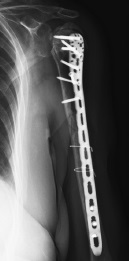

The control X-rays showed a consolidated fracture of the humeral diaphysis 9 months postoperatively, as well as the development of avascular necrosis of the left humeral head, nonunion, and migration of the greater tubercle into the subacromial space (Fig. 4). The shoulder function was limited, and the pain syndrome up to 5 VAS points persisted during movements, as well as a pronounced limitation of the amplitude of active movements with the abduction of up to 70°, flexion of up to 90°, external rotation of up to 0°, and internal rotation at the L5 level. However, the patient was fully adapted to daily activities.

Fig. 4. Shoulder control X-ray after 9 months since surgery: consolidation of the diaphyseal part, nonunion, secondary displacement of the greater tubercle and avascular necrosis of the humeral head